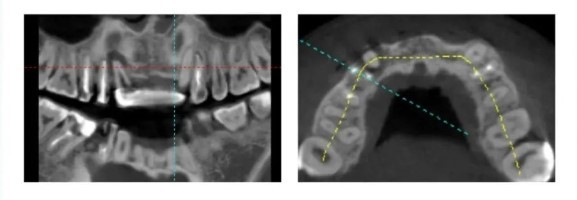

Radiological Examination - Preoperative CBCT

Observation: A3 shows a large-area radiopaque shadow at the root apex, and A4 exhibits bone destruction on the labial side and near the mesial aspect.

Sagittal section reveals bone deficiency in the labial wall near the mesial aspect of A4 and on the buccal side of A3, while the lingual wall remains intact. Adequate bone volume is observed for A2 and B2.

Three-dimensional reconstruction: Bone deficiency observed in the labial wall near the mesial aspect of A4 and on the buccal side of A3, while the lingual wall remains intact. Adequate bone volume is observed for A2 and B2.